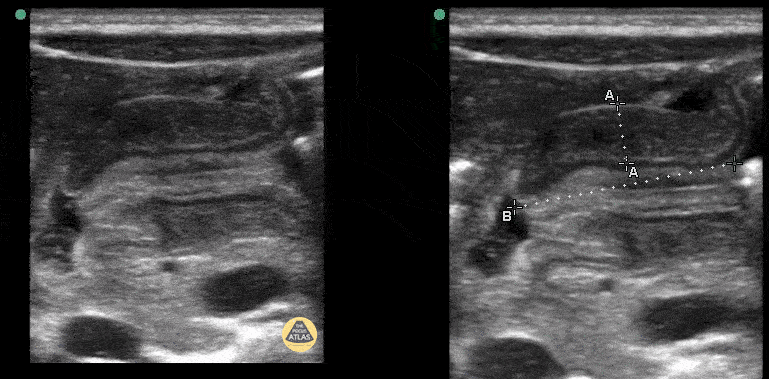

Roughly 1m male with projectile emesis. POCUS demonstrated elongated and thickened pylorus with absence of trans-pyloric flow. Contributor: Matthew Moake, MD PhD